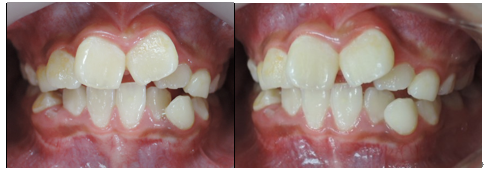

治療前 治療後

この様な歯並びの方はかなり見受けられるとと思われます。

当矯正歯科医院では、咬合バランスを改善する為には、

顎骨の拡大だけでは不十分と考ています。

その為、かみ合わせの高さなど立体的に改善していく事を心がけて日々治療しています。

今回も治療には、独自の方法とビムラー・t4k等を利用して改善しました。

今後、永久歯の歯並びは永久歯が萌えてから改善していく計画です。

顎骨のバランスは良好の為、永久歯を抜歯する必要は全くありません。